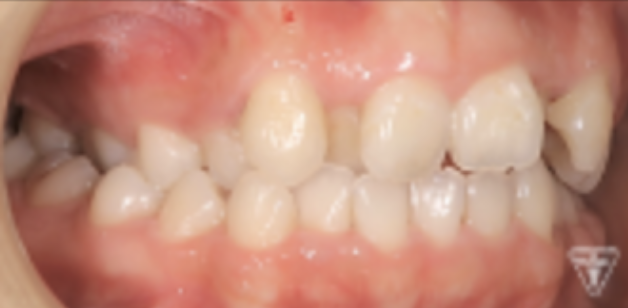

治療前